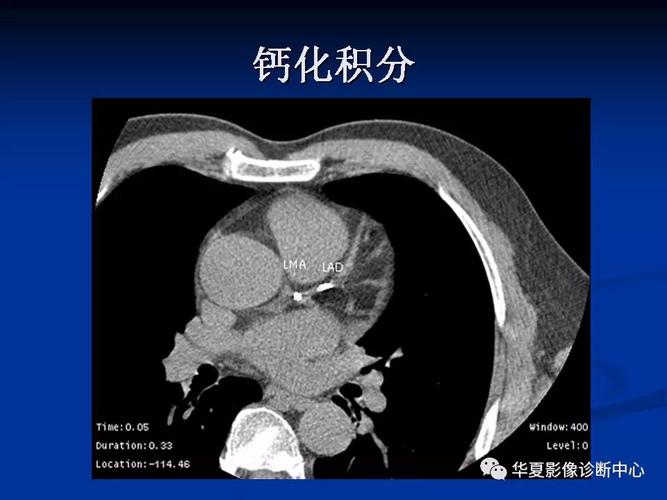

详细解读冠状动脉及冠心病ct

心脏ct断面解剖

带你全面了解心脏冠状动脉ct解剖

心脏解剖笔记:冠状动脉ct解剖及变异

冠脉ct图片讲解

冠脉ct图片讲解解剖图